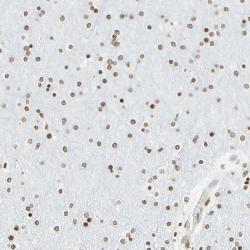

Supportive validation

- Experimental details

- Immunohistochemical staining of human cerebral cortex shows distinct nuclear positivity in glial cells.

- Validation comment

- Staining pattern consistent with experimental and/or bioinformatic data.